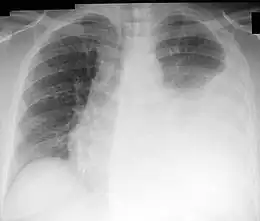

La ponction pleurale est généralement utile une fois le diagnostic d’épanchement pleural confirmé par la radiographie de thorax. De plus, l’analyse du liquide pleurale permet d’éliminer les étiologies nécessitant un drainage pleural urgent (par exemple lors d’une pleurésie purulente ou d’un hémothorax). C’est un acte peu invasif et les résultats de l’analyse du liquide pleural permettent une orientation étiologique dans 75 % des cas, ce qui implique un rapport bénéfices-risques assez élevé.

Une radiographie pulmonaire est réalisée avant l'opération; permettant de visualiser l'importance de l'épanchement et son côté. Comme avant la plupart des opérations, il est important de renseigner le patient sur les étapes de son déroulement. Une ponction pleurale se réalise sur un patient en position assise et en l'abordant par la partie postérieure de son thorax. Le niveau de la ponction est repéré par percussion de la paroi (matité). Après désinfection, l'anesthésie est effectuée. L'aiguille, munie d'une seringue, est insérée au niveau du site de la ponction, juste au-dessus de la côte inférieure, afin d'éviter nerfs et vaisseaux sanguins du paquet vasculo-nerveux qui se situe en dessous de la côte supérieure. Lorsque l'aiguille arrive au niveau de la plèvre (reflux de liquide) on effectue les prélèvements ou le drainage. L'aiguille est ensuite retirée d'un coup et un pansement est mis en place. Une échographie pleurale est parfois réalisée en même temps, ou peu avant pour guider plus facilement la ponction pleurale, permettant d'avoir un taux de complication moindre[2],[3]. Cette technique est particulièrement intéressante en cas d'un épanchement de petite taille ou cloisonné[4].

Après l'opération, il est important de surveiller les constantes du patient. Une radio pulmonaire de contrôle est réalisée pour contrôler le niveau de l'épanchement et l'absence de pneumothorax, mais son utilité dans les cas simples reste discutée[5].

- la plus fréquente est un pneumothorax, survenant dans environ 6 % des cas et nécessitant une évacuation dans un tiers des cas[6]. Il survient en cas de ponction accidentelle du poumon ou d’une entrée d’air au travers de l’aiguille. Il peut être détecté par une radiographie de thorax de contrôle post ponction, montrant typiquement un liseré horizontal. les formes modérées se résorbent le plus souvent par elles-mêmes. Les pneumothorax sont plus rares si le médecin est expérimenté ou si le geste est guidé par une échographie[6] ;